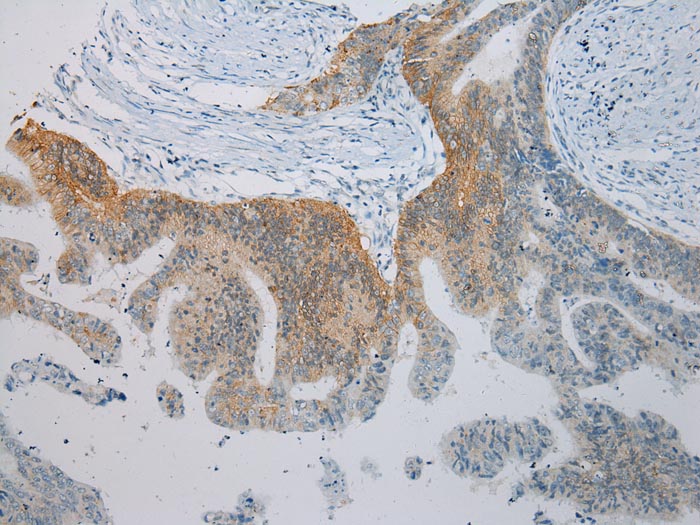

Immunohistochemical analysis of paraffin-embedded Human Colorectal cancer tissue using #43337 at dilution 1/100.